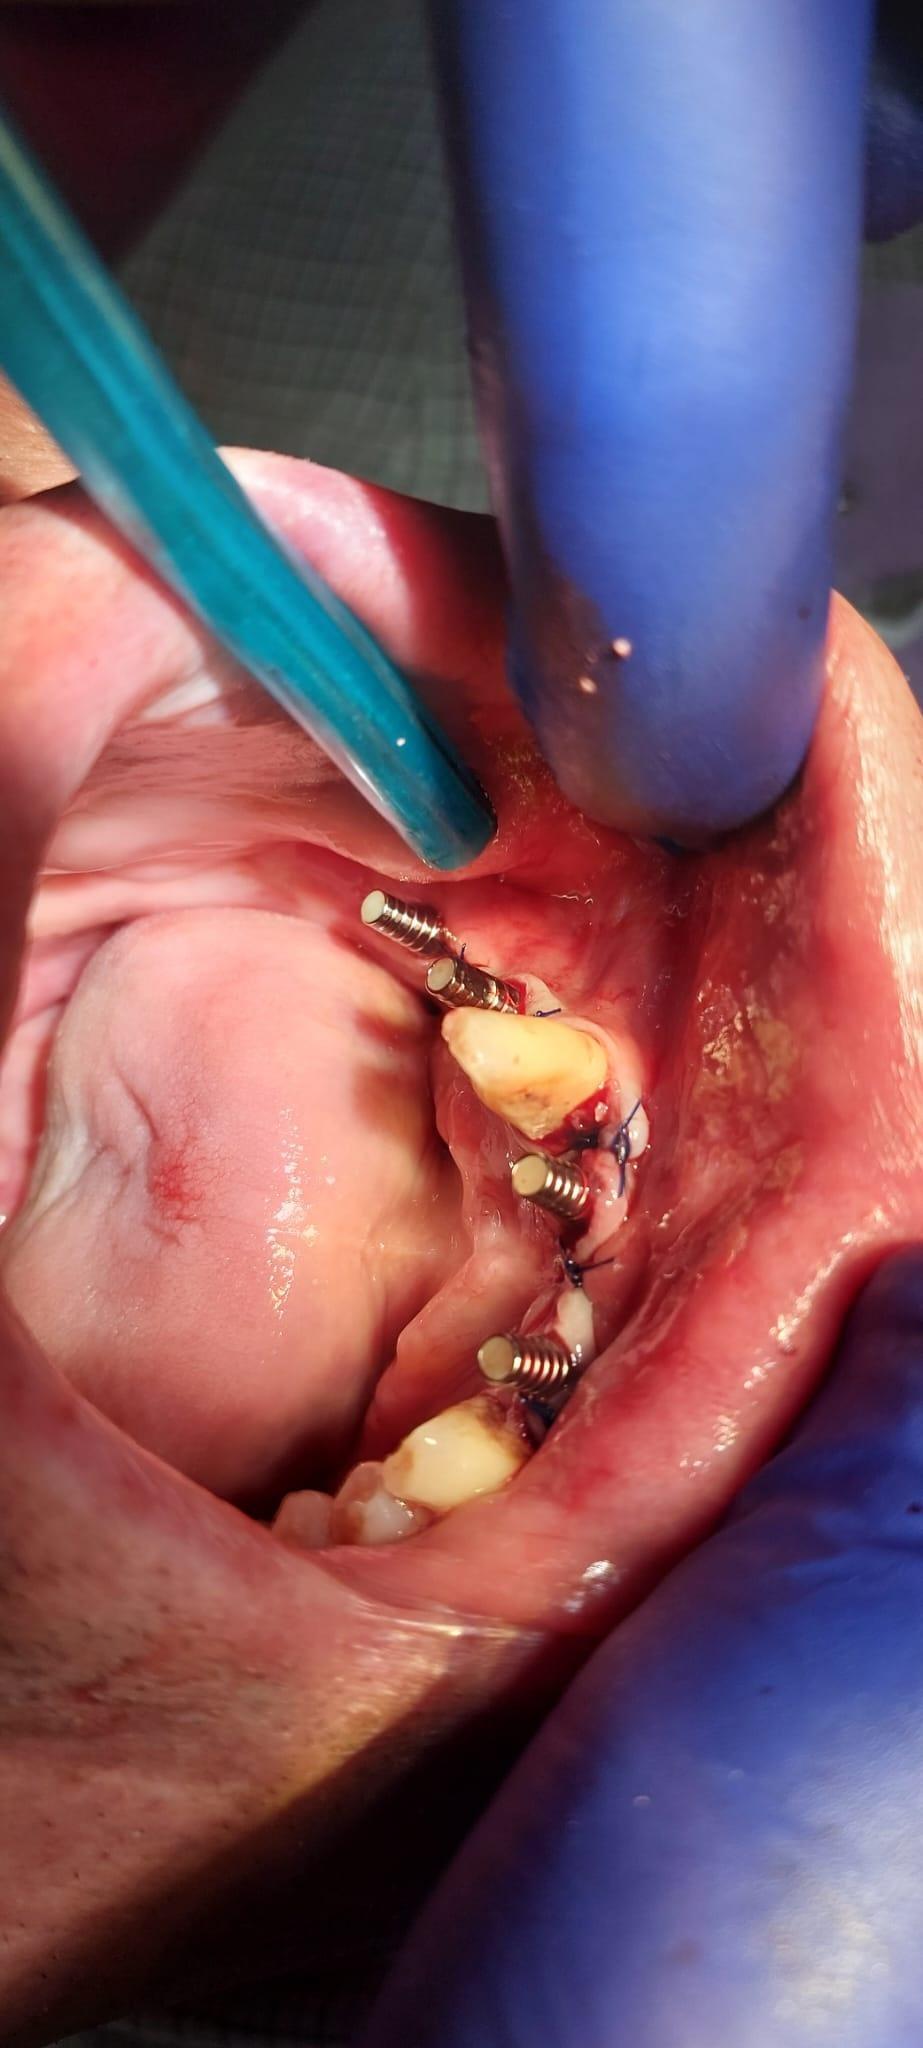

Boala parodontala are un caracter progresiv. Pentru cazurile mai grave, recomandam tratamentul parodontal chirurgical rezectiv sau regenerativ.

IMPLANTOLOGIE

SUPRAPROTEZAREA PE IMPLANT